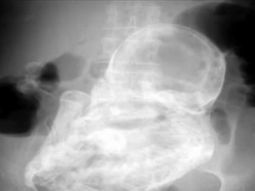

El procedimiento, en el que se unieron tendones, arterias y nervios, implicó además la reconstrucción de la estructura ósea, tanto de la mano amputada como de la muñeca. Asimismo, durante el post operatorio se realizaron todos los estudios correspondientes para evaluar la actividad fetal, con resultados normales. Romina espera una nena y ya no duda del nombre: se llamará Alma Milagros.

Los médicos le permitieron pasar Noche Buena y Navidad en su casa pero esta semana volvió a la clínica. El alta lo recibirá en unos días, después de someterse a una de las dos operaciones que le restan: la primera para restablecer la sensibilidad y lograr una fijación ósea definitiva; y la otra y última, de tipo estética, que se llevará a cabo más adelante.

Mientras tanto, está aprendiendo a utilizar la mano izquierda, porque más allá de que el reimplante haya sido exitoso, es muy difícil que recupere la motricidad fina, que permite, por ejemplo, una escritura delicada o el movimiento suave de los dedos. "Con rehabilitación logrará recobrar la fuerza para tomar objetos más grandes como un vaso o un teléfono", indicó Escudero.

Según explicó, en la próxima cirugía se volverán a suturar los nervios, y dependiendo del estado en el que se encuentren, quizás se extraigan algunos de la pierna. "Habrá que esperar entre 6 meses y un año para que la paciente recupere la sensibilidad al tacto", precisó el cirujano, quien trabaja con un equipo integrado por el traumatólogo Matías Caracciolo y los residentes de Traumatología y Plástica Reconstructiva, Martín Lovagnini y Martín Salas, respectivamente.